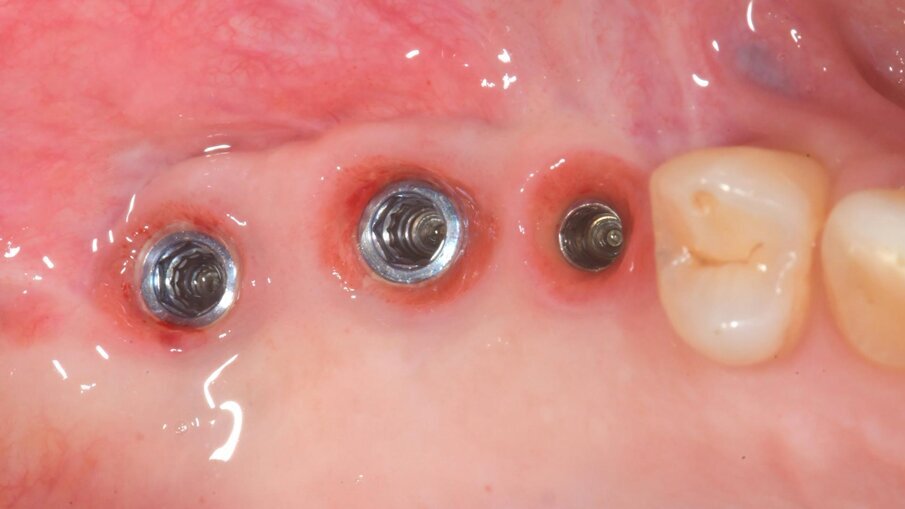

Dopo 9 mesi, è stata eseguita una seconda CBCT per valutare il volume di osso rigenerato e per pianificare la chirugia computer guidata (Fig. 23); i file .STL ottenuti dalla scansione 3D e i files .DICOM della CBCT sono stati utilizzati per pianificare l’inserimento degli impianti tramite una chirurgia computer guidata (Navimax, Biomax) (Fig. 24) . Il giorno della chirurgia implantare (T1), è stata eseguita un’incisione orizzontale para-crestale, per permettere l’esposizione della griglia e la sua rimozione, previa rimozione delle viti in titanio e dell’osso formatosi al di sopra di essa (Figg. 25, 26). L’esame clinico ha evidenziato una completa rigenerazione ossea del difetto osseo verticale, con assenza di pseudo-periostio o pseudo-periostio minore di 1 mm, di conseguenza pseudo-periostio di “classe 1” secondo la classificazione di Cucchi et al.20 (Figg. 27, 28). Successivamente, la dima chirurgica è stata posizionata e fissata nella posizione pianificata; i siti implantari sono stati preparati con frese progressive dedicate; e tre impianti conici (T3, Zimvie) sono stati inseriti nelle posizioni #15, #16 e #17, secondo la pianificazione protesicamente guidata eseguita precedentemente mediante il software da chirurgia guidata (Figg. 29-31). Gli impianti sono stati “sommersi”, attendendo la corretta osteointegrazione, ed è stata eseguita una chiusura per prima intenzione (Fig. 32). Dopo il posizionamento degli impianti, è stata eseguita una radiografia OPT (Fig. 33).

Dopo 3 mesi (T2), gli impianti sono stati esposti mediante un lembo spostato apicale per aumentare la quantità di tessuto cheratinizzato vestibolarmente agli impianti e riallineare la linea mucogengivale precedentemente spostata in direzione palatale; e sono state applicate viti di guarigione svasate per favorire una corretta guarigione trans-mucosa. Dopo 1 mese (T3), sono state eseguite corone singole in ceramica, per il primo carico funzionale e la finalizzazione provvisoria del caso, in attesa della maturazione ossea completa (Fig. 34). Dopo 6 mesi (T4), le corone sono state sostituite con corone in zirconio, per il carico funzionale e la finalizzazione definitiva degli impianti (Figg. 36-38). I controlli clinici e radiografici al primo carico funzionale, a 6 mesi, a 12 mesi, e a 24 mesi, mostrano la salute dei tessuti peri-implantari e il mantenimento dei livelli ossei peri-implantari (Fig. 39).